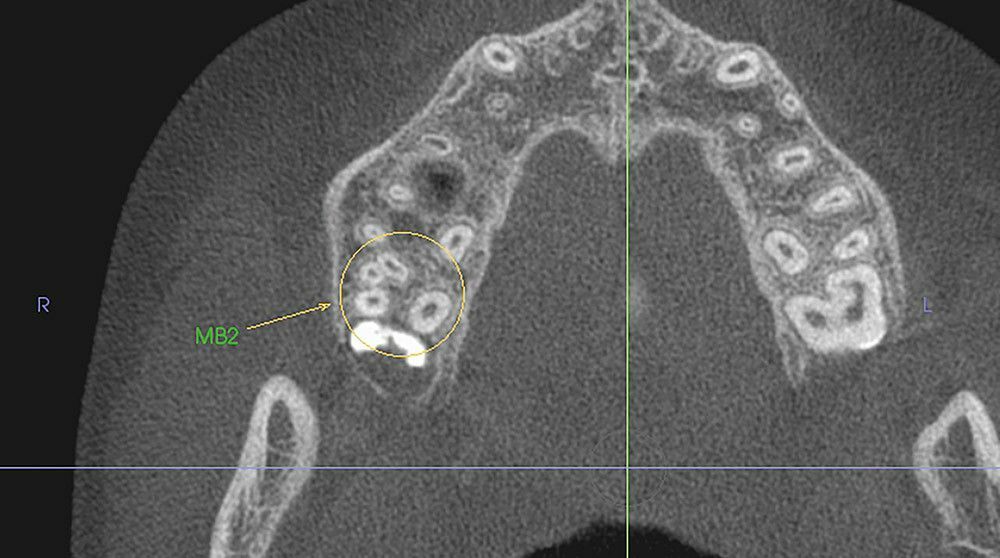

Эндодонтия: оценка корня зуба в трех измерениях